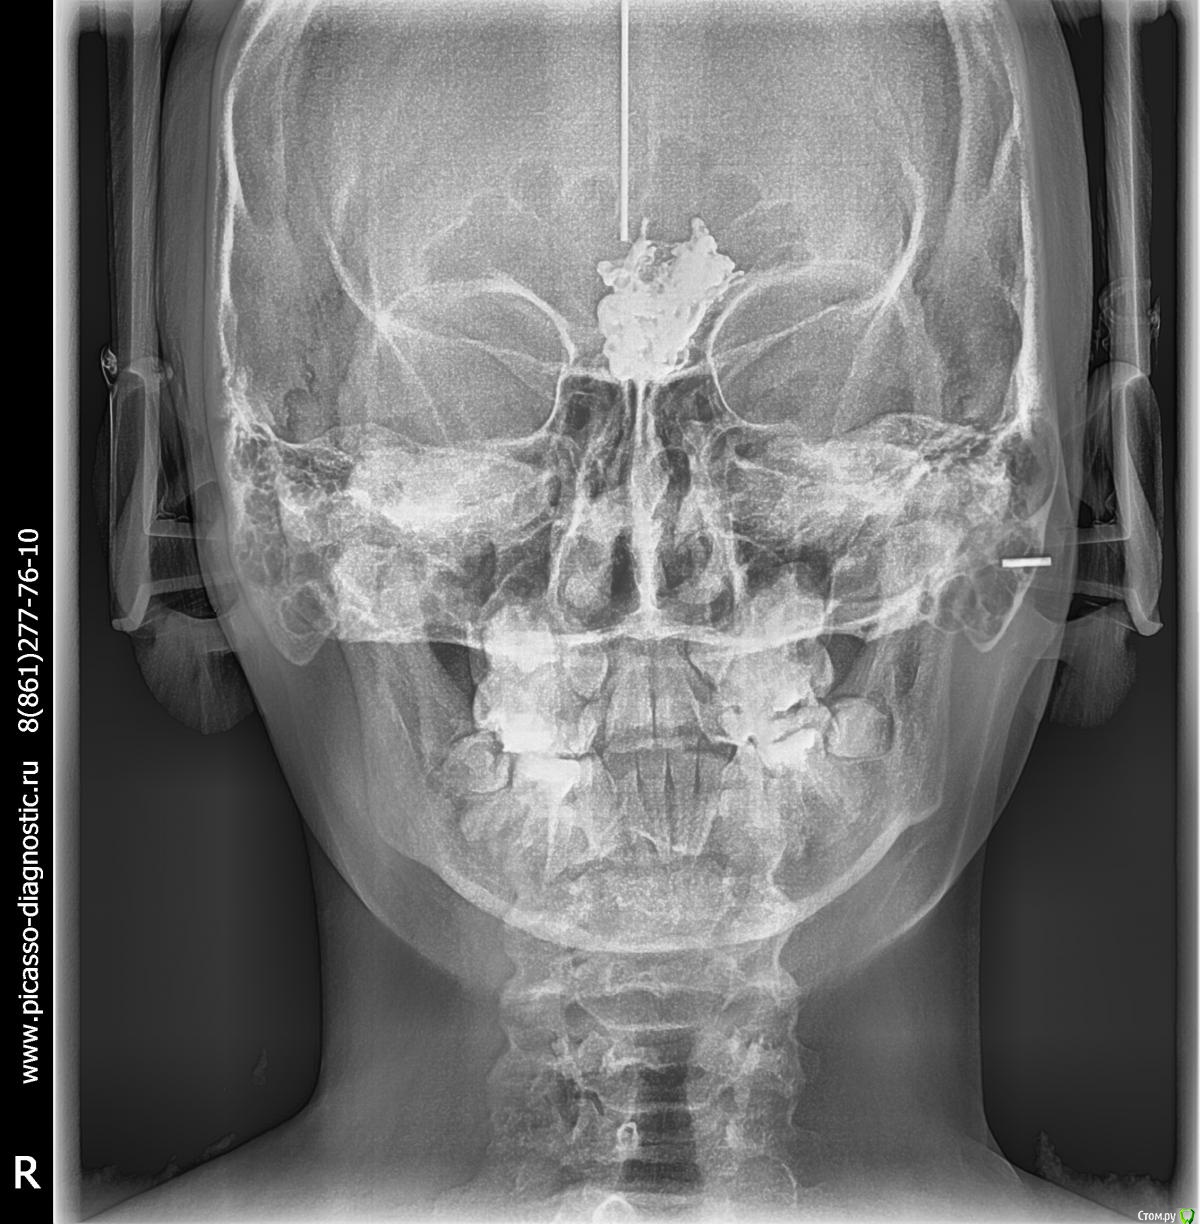

vov4ikdent Опубликовано 30 января, 2018 Поделиться Опубликовано 30 января, 2018 Коллеги, случайная находка на ТРГ. Что это? Никогда такого не видел. Ссылка на комментарий

kramer Опубликовано 30 января, 2018 Поделиться Опубликовано 30 января, 2018 Жалоб не было, сел расчет делать и увидел. Кт надо же как-то обосновать, что сказать родителям. Пациентка девочка 14 лет. Назначена на пятницу. Думаю, куда на консультацию направить.Ну явно какая-то сосудистая мальформация. Радиоплотность должна говорить о кальцификации. имхо 2 Ссылка на комментарий

kramer Опубликовано 30 января, 2018 Поделиться Опубликовано 30 января, 2018 (изменено) Показал знакомому нейрохирургу, он предположил краниофарингиому. Девочке нужна консультация нейрохирурга и обследование Изменено 30 января, 2018 пользователем kramer 2 Ссылка на комментарий